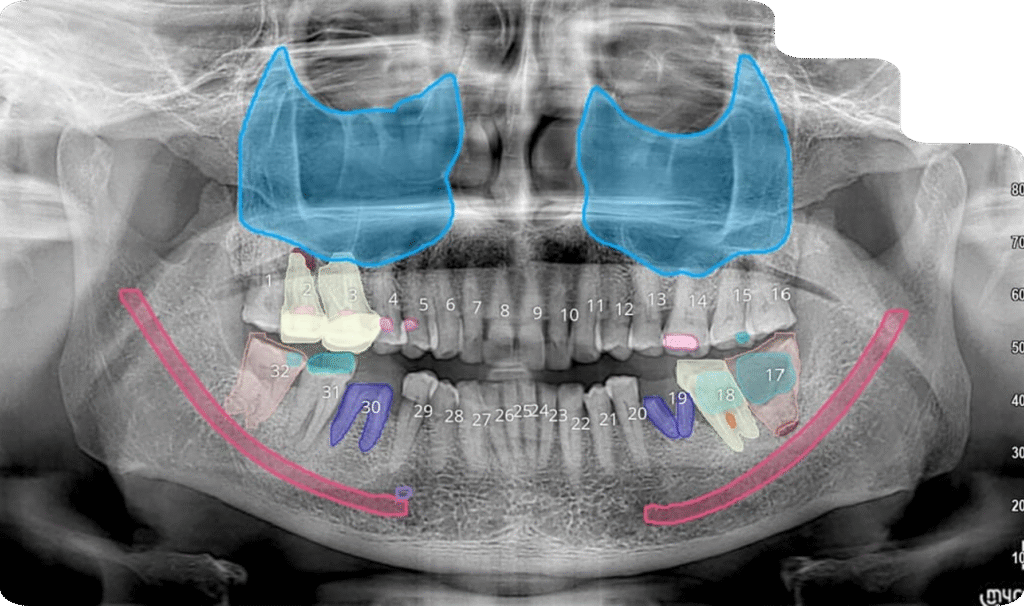

Instant AI OPG Analysis: A Powerful Screening Tool for Dentists

Embrace the power of artificial intelligence for immediate clinical insights. Our AI OPG reporting service provides dentists with an automated, preliminary analysis of panoramic X-rays in minutes. It is designed as a highly efficient screening tool to support your own clinical evaluation, helping you quickly identify areas of potential concern.

Instant Turnaround: Receive a preliminary report in the lowest TAT, 24/7.

Enhanced Efficiency: Dramatically speed up the screening process in high-volume environments.

Objective Screening: Leverage unbiased AI analysis to flag potential caries, bone loss, periapical lesions, and calculus.

Clinical Decision Support: Use the AI findings as a map to guide your own comprehensive clinical examination.